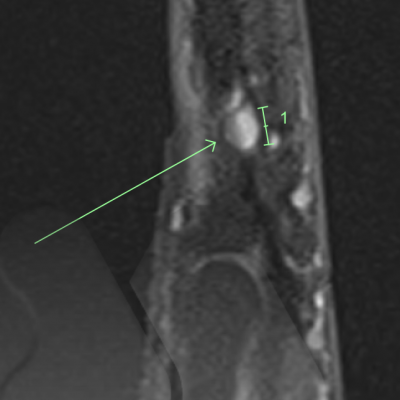

This is a rare benign (non-cancerous) growth often under the fingernail or fingertip pulp and can involve bone.

It commonly causes severe pain in the fingertip in cold environments and extreme pain and sensitivity to touch. X-Ray and MRI can be useful tests in confirming the diagnosis.